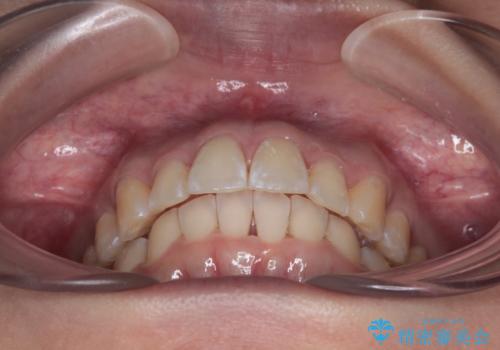

前に飛び出して目立っている前歯を整える インビザライン矯正治療

- 前方に主張した前歯2本を気にして来院された患者様です。

下顎前歯がデコボコしており、その影響で上顎前歯が前方に押し出されている状態でした。

口元が閉じにくいという印象はなかったため、非抜歯矯正にて歯列を整えていくこととしました。

上下左右の親知らずを抜歯し、上下ともに歯列を後方と側方に拡大し、口元を突出させることなくデコボコを解消することとしました。

前歯の形が台形であり、歯列が整ったところでブラックトライアングルが目立つ仕上がりとなったため、IPR(歯と歯の間を削る処置)によって歯の形態を修正し、隙間の目立たない歯列に仕上げることができました。